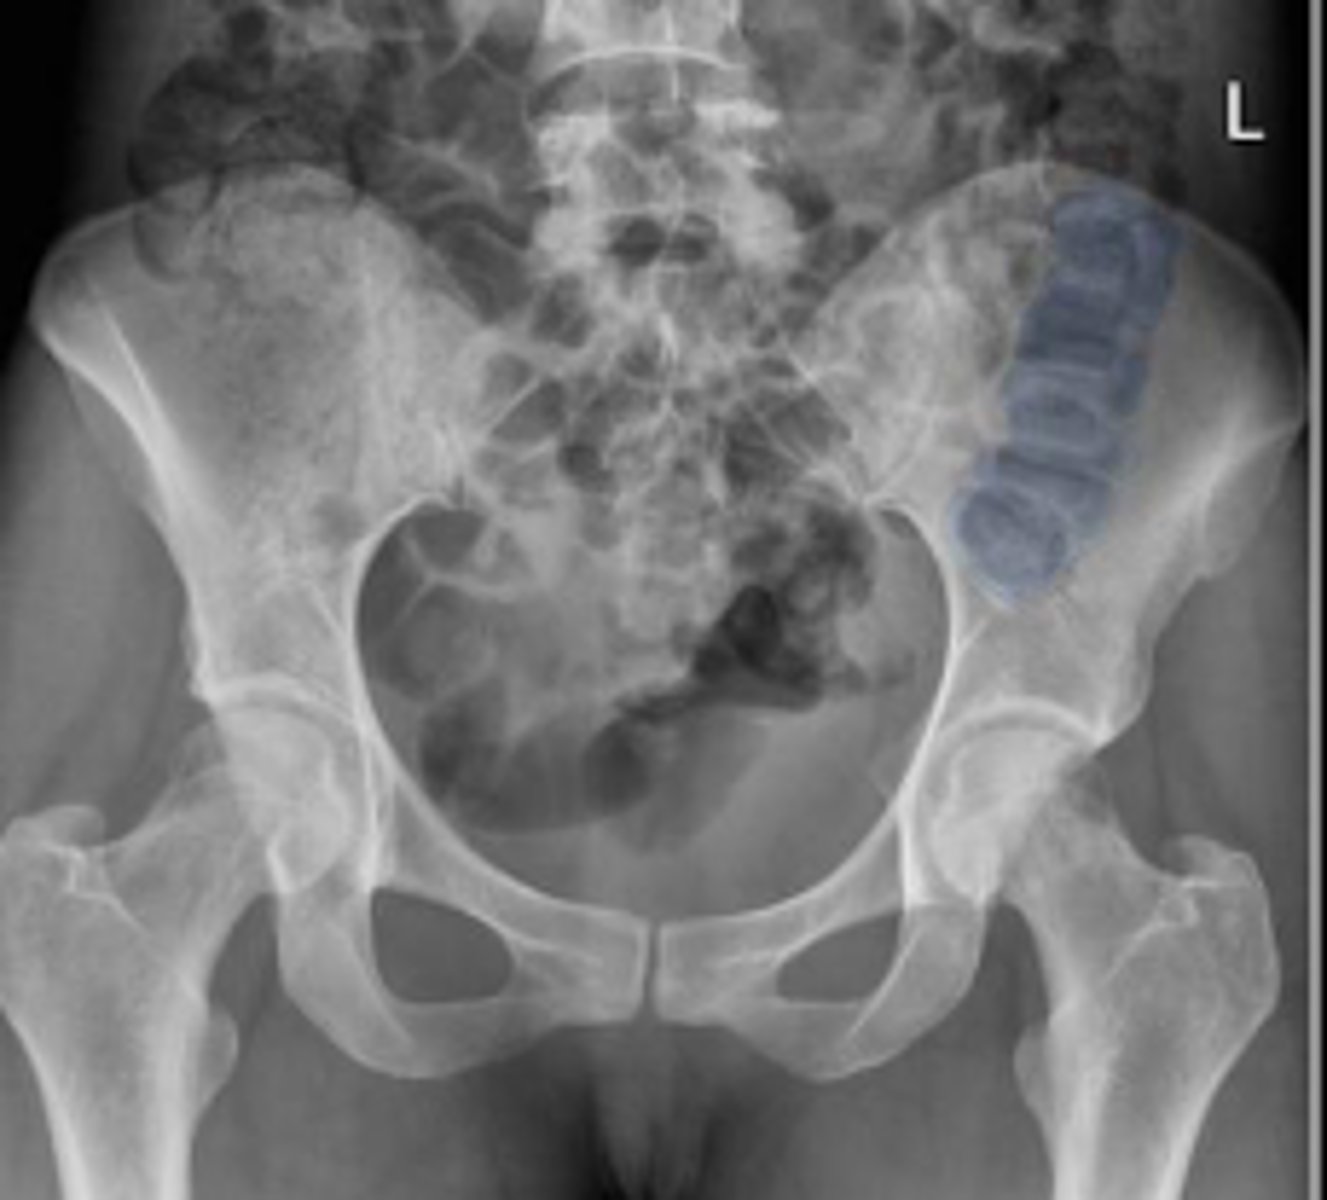

Bilateral frog leg view

What is the name of the radiographic view?

Sigmoid colon

What is outlined?